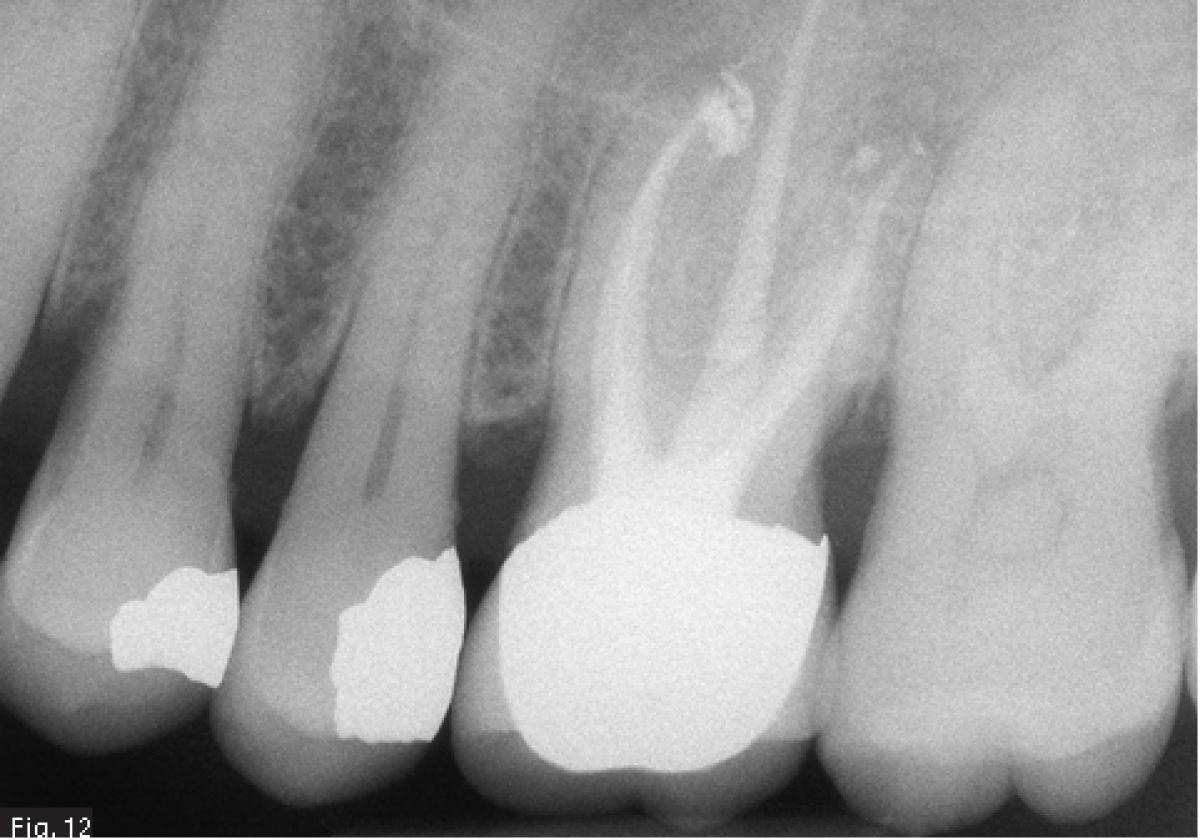

A 62 years old patient was referred to our clinic for endodontic retreatment: the patient reported swelling to the upper left part of the gum. The radiographic examination showed the presence of an existing endodontic therapy and of periapical radiolucencies (Fig. 1). Since the existing therapy could be improved, we decided to retreat the tooth passing through the existing crown. After positioning the rubber dam (Fig. 2), the existing composite filling in the centre of the crown was removed by using a diamond-coated bur driven by a high-speed handpiece. In this way, the access cavity was executed and refined in order to see the pulp chamber(Fig. 3). The existing root canal filling was removed thanks to the use of rotary instruments specifically designed for retreatment, then ultrasonic tips were used to remove the remnants of the pull chamber floor. The chamber was filled with 5 % sodium hypochlorite (Fig. 4) and the MB2 canal, that had not been shaped-cleaned-filled during the initial treatment, was found and it underwent the standard protocol for shaping.

Considering the presence of an endodontic lesion and swelling, a lot of time was dedicated to decontamination of the root canal system (Fig. 5) (18). The device chosen to deliver the irrigating solution right to the working length was IrriFlex (Produits Dentaires SA, Switzerland) (Fig. 6) because, thanks to its flexibility, it was able to deliver the irrigant to the apical third of each root, without any effort, without stopping in case of curvatures. The irrigant was then activated by means of ultrasonic inserts (19) according to the indications given by Tonini et al. (12). After ensuring that the root canals were dry, they were filled according to the warm gutta percha compaction technique (Fig. 8-10). After that, the access cavity was filled by means of a direct composite restoration (Fig. 11) and a post operative x-ray was taken in order to check the final result (Fig. 12).